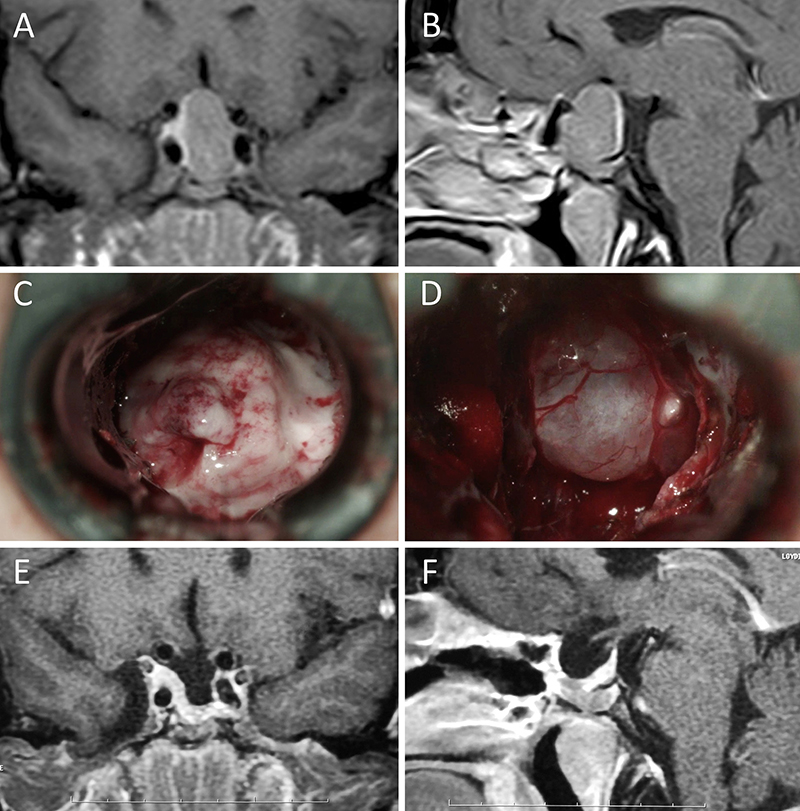

Figura 2: Macroadenoma no funcionante en mujer de 31 años. La paciente presentó en el preoperatorio déficit visual que mejoró tras la cirugía. A-B: RM preoperatoria; C-D: intraoperatorio; E-F: RM postoperatoria.

Figura 3: Macroadenoma no funcionante en un hombre de 64 años. El paciente presentó en el preoperatorio déficit visual que mejoró tras la cirugía. A-B: RM preoperatoria; C-D: intraoperatorio; E-F: RM postoperatoria.

Figura 4: Macroadenoma no funcionante en mujer de 32 años. La paciente presentó en el preoperatorio déficit visual que mejoró tras la cirugía. A-B: RM preoperatoria; C-D: intraoperatorio; E-F: RM postoperatoria.